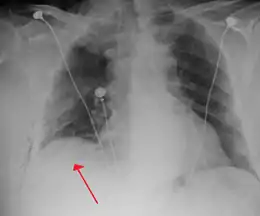

A chest tube placed on the right for a pneumothorax

A chest tube (or intercostal drain) is the most definitive initial treatment of a pneumothorax. These are typically inserted in an area under the axilla (armpit) called the "safe triangle", where damage to internal organs can be avoided; this is delineated by a horizontal line at the level of the nipple and two muscles of the chest wall (latissimus dorsi and pectoralis major). Local anesthetic is applied. Two types of tubes may be used. In spontaneous pneumothorax, small-bore (smaller than 14 F, 4.7 mm diameter) tubes may be inserted by the Seldinger technique, and larger tubes do not have an advantage.[15][47] In traumatic pneumothorax, larger tubes (28 F, 9.3 mm) are used.[41] When chest tubes are placed due to either blunt or penetrating trauma, antibiotics decrease the risks of infectious complications.[48]

Chest tubes are required in PSPs that have not responded to needle aspiration, in large SSPs (>50%), and in cases of tension pneumothorax. They are connected to a one-way valve system that allows air to escape, but not to re-enter, the chest. This may include a bottle with water that functions like a water seal, or a Heimlich valve. They are not normally connected to a negative pressure circuit, as this would result in rapid re-expansion of the lung and a risk of pulmonary edema ("re-expansion pulmonary edema"). The tube is left in place until no air is seen to escape from it for a period of time, and X-rays confirm re-expansion of the lung.[15][19][33]